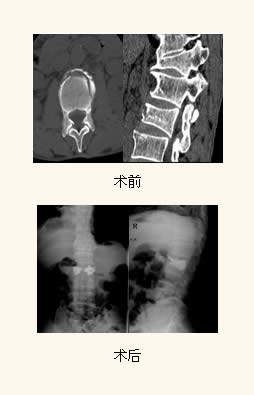

微创手术—经皮椎体成形术(PercutaneousVertebroplasty,PVP)是指经皮通过椎弓根或椎弓根外向椎体内注入骨水泥以达到增加椎体强度和稳定性,防止塌陷,缓解疼痛,甚至部分恢复椎体高度为目的一种微创脊椎外科技术。